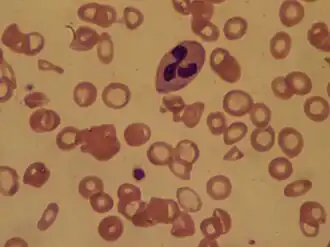

A alteração mais perceptível no sistema circulatório é o abrandamento da circulação sanguínea nos membros inferiores, o que leva ao aumento da pressão nas veias e estagnação do sangue nas pernas. Estas alterações são provocadas pela compressão da veia cava inferior pelo útero e pelo aumento da produção de hormonas. Embora sejam cada vez mais proeminentes ao longo da gravidez, podendo causar varizes e inchaço das pernas, estas alterações geralmente desaparecem após o parto. A pressão do útero em crescimento nos vasos linfáticos da pélvis provoca a diminuição da drenagem linfática das pernas, o que causa inchaço e dilatação das pernas e pés. O inchaço generalizado noutras partes do corpo é geralmente um sinal de alarme. O volume plasmático aumenta progressivamente a partir da sexta semana e o volume de hemácias aumenta depois da oitava semana. Ambos os volumes tornam-se estáveis nas últimas semanas, mas, como o aumento do volume plasmático é mais precoce e tende a ser mais acentuado do que o aumento do volume de hemácias, ocorre um efeito de diluição responsável pela chamada anemia fisiológica da gravidez. A alteração dos fatores de coagulação prepara o organismo da mulher para o momento do parto, permitindo controlar rapidamente eventuais hemorragias, embora durante a gestação e puerpério aumente o risco de trombose.[1][48]

No termo da gravidez, a quantidade de sangue de uma mulher grávida é aproximadamente 25% superior em relação ao estado de não gravidez, de modo a preencher os vasos do útero, a transportar uma maior quantidade de oxigénio e nutrientes para o feto e servir de reserva em caso de hemorragias. Este aumento é consequência do aumento do número de glóbulos vermelhos (20%) produzidos na medula óssea e pelo aumento do volume do plasma (30%), causado pela retenção de líquidos. Esta diferença de valores faz diminuir a viscosidade do sangue e causa uma anemia aparente.[1]

Análises ao sangue

Na primeira consulta são geralmente realizadas análises ao sangue de rotina a todas as grávidas. Se a grávida fizer parte de um grupo de risco, podem ser adicionalmente realizadas análises a biomarcadores específicos. Nas situações em que a grávida apresenta um risco acrescido de síndroma de Down, por volta das dez semanas são realizadas análises para determinar o nível das hormonas fetais, da proteína plasmática associada à gravidez (PAPP-A) e da gonadotrofina coriónica humana (HCG). Por volta das dezasseis semanas, algumas instituições de saúde realizam análises adicionais. Dependendo da instituição e do risco da gravidez, podem ser requisitadas análises para medição da alfafetoproteína (AFP), uma análise tripla (AFP, HCG e estriol) ou uma análise quádrupla (que também analisa a inibina-A).[72] Quando o fator Rh do sangue da mãe é negativo e existe a possibilidade de doença de Rhesus, geralmente confirma-se a presença de anticorpos antiRh no sangue.[73]

Um valor elevado de alfafetoproteína no sangue da grávida indica uma maior probabilidade de doenças do tubo neural como espinha bífida, anencefalia e outras anomalias no feto. Por outro lado, um valor baixo de alfafetoproteína no sangue em conjunto com um valor elevado de gonadotrofina coriónica humana e um valor baixo de estriol indicam uma maior probabilidade de síndrome de Down. No entanto, existem outras causas que explicam valores elevados: erro no cálculo da idade gestacional, a existência de mais do que um feto, ameaça de aborto ou morte do feto. Em caso de valores elevados, geralmente é recomendada a realização de uma ecografia. No entanto, em 2% dos casos a ecografia não revela a causa do aumento dos valores, situação em que se recomenda a realização de uma amniocentese para medir os valores de alfaproteína no líquido amniótico.[74]